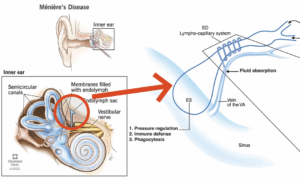

頸椎、側頭骨、顎関節および上顎骨の変形と緊張を含む頭蓋頸椎不安定性は、内耳のリンパ排出を停滞させ、内リンパ水腫を引き起こす構造的原因として、繰り返されるメニエール病の隠れた原因となる可能性があります。

「6年前に初めてメニエール病を発症し、周期的にめまいが発生して日常生活が困難です。ひどいめまいが起こると家の外に出ることもできず、ほとんど横になっているしかないほど何もできませんでした。利尿剤などを服用していますが、耳閉感、耳圧迫感が消えず続いています。」